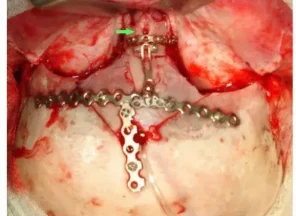

Иссечение дермальных синусов, дермоидных кист и перикраниальных синусовРазличают краниальный и спинальный дермальный синусы. Дермальный синус может заканчиваться как в мягких тканях, так и проникать в полость черепа или позвоночного канала. В последних случаях имеется высокий риск развития менингита. Лечение только хирургическое, проводится полное иссечение синуса. При распространении синуса до твердой мозговой оболочки свищ иссекается вместе с окружающим участком твердой мозговой оболочки. Дефект твердой мозговой оболочки герметично ушивается.